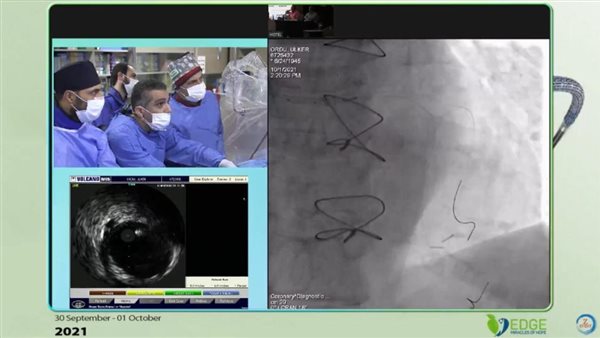

لأول مرة.. نجاح زراعة دعامات مغطاة للشريان الأورطي تحت مظلة التأمين الصحي ببورسعيد

«الرعاية الصحية»: كفاءة الطبيب المصري لا تقل عن نظرائه في الدول المتقدمة

03/10/2021 12:06 م